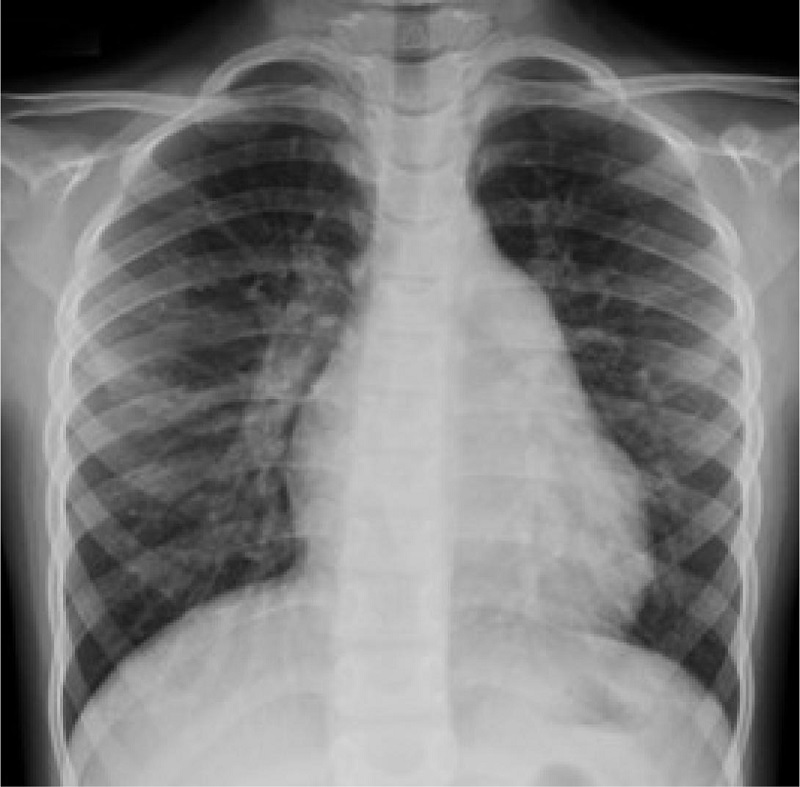

Chest Radiography

Chest radiography shows increased pulmonary vascular markings, no pulmonary edema, and mild cardiomegaly with cardiothoracic ratio of 0.55 (Figure 1).